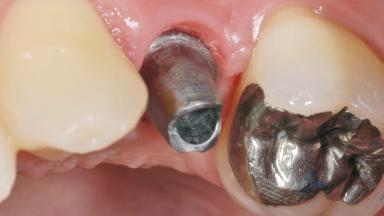

In 2004, a 36-year-old male patient, a non-smoker, presented due to acute pain in the premolar region of the upper left jaw. An orthopantomograph revealed that tooth 24 had been endodontically treated. It also became evident that, during root-canal filling,endodontic filling material had been pushed beyond the apex. This material was located very close to the maxillary sinus floor. Due to this finding in combination with the severe pain and a possible root fracture, tooth 24 was extracted. The esthetic expectations of the patient were not too high and his individual esthetic risk profile summed up to a medium risk profile.